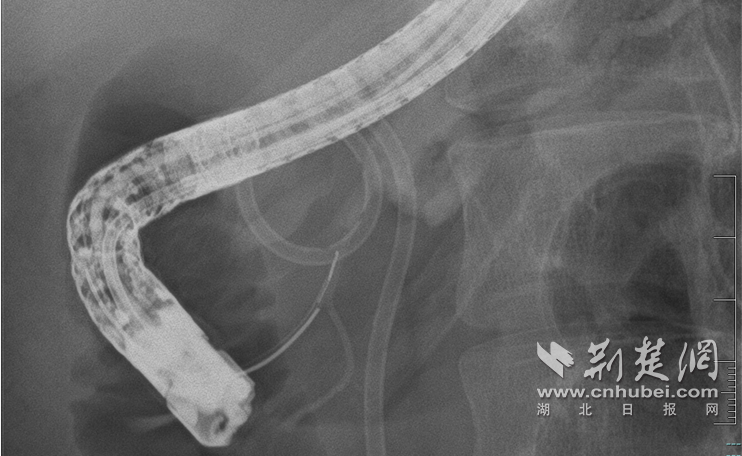

圖為內(nèi)鏡下微創(chuàng)修復(fù)斷裂的胰管

面對這一難題,大家決定迎難而上,在內(nèi)鏡下微創(chuàng)修復(fù)斷裂的胰管。10月30日,手術(shù)術(shù)中造影清晰地顯示了病情的復(fù)雜程度:胰頭部胰管扭曲,胰管在頸部完全中斷,形成一個直徑約2厘米的囊腔,遠(yuǎn)端的胰體尾部胰管因堵塞而顯著擴(kuò)張。

技術(shù)的難點(diǎn)在于空間定位。在醫(yī)療團(tuán)隊(duì)成員的緊密配合下,覃華和雒真龍副主任醫(yī)師在X光引導(dǎo)下,將導(dǎo)絲小心翼翼地通過囊腔,精準(zhǔn)找到遠(yuǎn)端胰管細(xì)如發(fā)絲的斷端開口,實(shí)現(xiàn)了斷裂管道的“勝利會師”!隨后,專家們順利置入支架,為他重建了胰液引流通道。